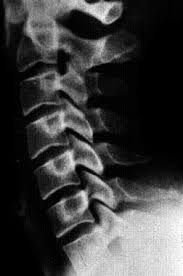

backpack lordosis

backpack lordosis An observational study by Young, Haig and Yamakawa (2006) of 184 middle-school children investigated a possible relationship between back pain and backpack weight. The study did not find a correlation between backpacks and incidence of LBP, but 35.9% of all of the students surveyed reported having back pain in the cervical, thoracic or lumbar region. The researchers acknowledged that for children with back pain, wearing a backpack could make the condition more uncomfortable, and that a strategy of reducing the frequency of wearing a backpack or the load carried might be a viable option in such cases. Ippolito, Versari and Lezzerani (2006) reviewed the literature concerning clinical aspects and rehabilitation of different types of juvenile LBP disorders. The most common causes of LBP in children were found to result from mechanical, developmental, inflammatory, neoplastic and psychosomatic factors.

Under mechanical cause, the literature found that in some cases faulty posture develops in older children with exaggerated lumbar lordosis. Poor postural habits may be linked to prolonged television watching or inappropriate school furniture. Strategies such as stretching and strengthening exercises may improve postural abnormalities. In a study by Petersen, Bergström and Brulin (2003), a random sample of 1,155 children completed a questionnaire. Recurrent monthly backache was reported by 18% of the children, with approximately half of them having weekly complaints. The prevalence of recurrent backache showed a large variation by grade, not by gender. The results suggested a need for preventive efforts addressing these complaints at an early age. Geldhof and associates (2007) studied classroom postures of 41 children, aged 8–12. Data revealed that 55% of the children complained of neck region pain and 45% reported pain in the thoraco-lumbar region. Analysis showed that children who spent more time sitting with the trunk flexed over 45 degrees reported significantly more thoraco-lumbar pain.